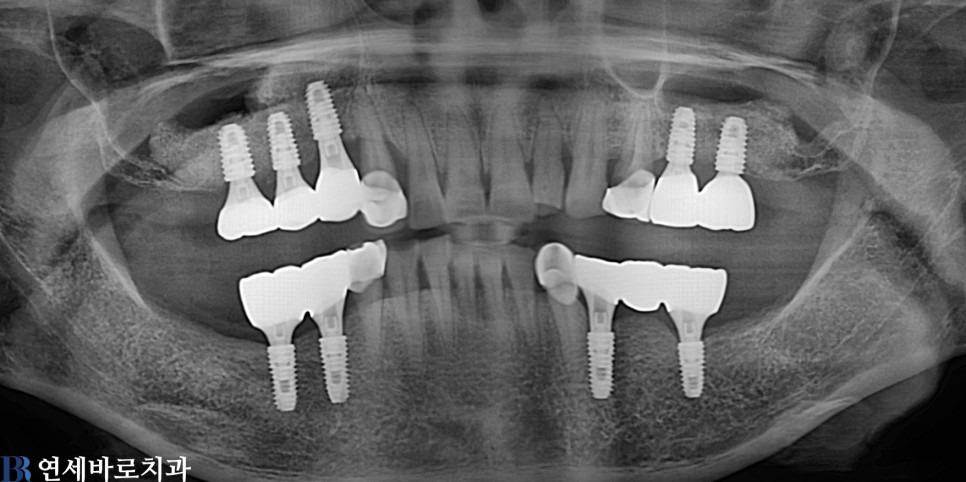

임플란트

어금니 전체 임플란트 #5